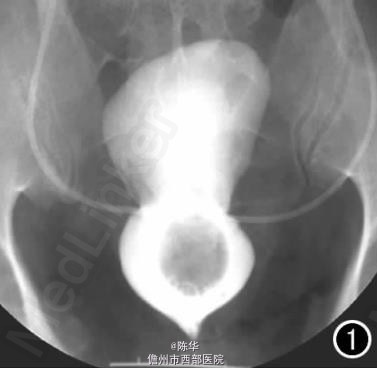

腹部B超示双肾增大,双肾慢性肾病声像;双肾中度积液伴双输尿管上段扩张。 IVPshi双侧输尿管中或下段梗阻。 膀胱造影:经尿道置管后,注射对比剂充盈膀胱,膀胱下半部先充盈,继续灌注对比剂后见膀胱完全显影,膀胱形态异常,呈“倒葫芦状”(图1)。 CT增强扫描行延迟期 MPR重组,见双侧肾盂、肾盏扩张积液;双侧输尿管纡曲、扩张,下端呈鸟嘴样变窄;膀胱变形、体积减小(图2); MRI平扫示双侧肾盂、肾盏扩张积液,双侧输尿管扩张并下端鸟嘴样变窄,盆腔内多量脂肪沉积,分布于膀胱、直肠周围,T1WI、T2WI呈明显高信号,T2WI抑脂像呈稍高信号,膀胱受压变形、体积减小(图3a~c); MRU示双侧肾盂肾盏扩张、积液,双侧输尿管显著纡曲、扩张,下端鸟嘴样变窄,管壁光整,膀胱变形、体积较小、位置抬高(图3d)。